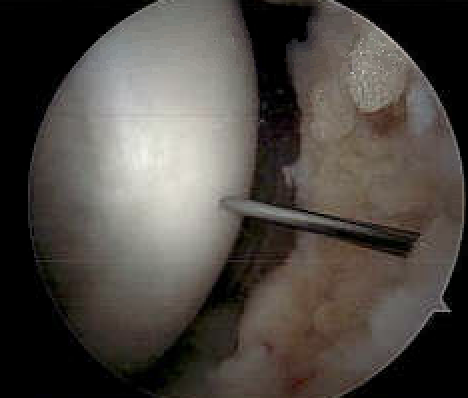

Cartilage intact on arthroscopy

In a stage 1 lesion there is no cartilage breach

- the MFC / LFC looks normal

Transarticular drilling of LFC OCD

Transarticular drilling of MFC OCD